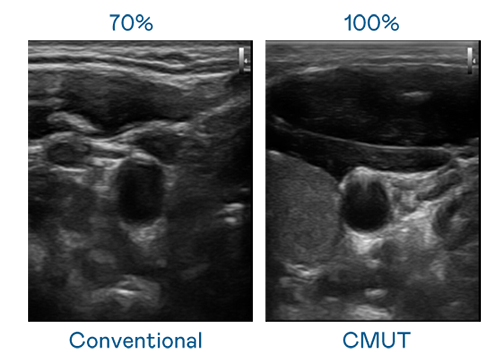

CMUT 技术是一种用电容式微机电元件来产生超音波讯号的技术。与传统 PZT 压电式技术相比,CMUT 频宽增加 30%,更宽频的超音波讯号让影像解析度大幅提升,是实现高影像品质医疗超音波扫描、促进精准医疗发展的关键技术。

超音波影像的解析度高低,首先取决于探头能发出的讯号频宽。J9九游 CMUT 可提供高清晰的超音波讯号,提供高频宽、高灵敏度、影像纹理细节更高的超音波影像,协助医护人员缩短影像判读时间及利用精准的医疗影像进行诊断。